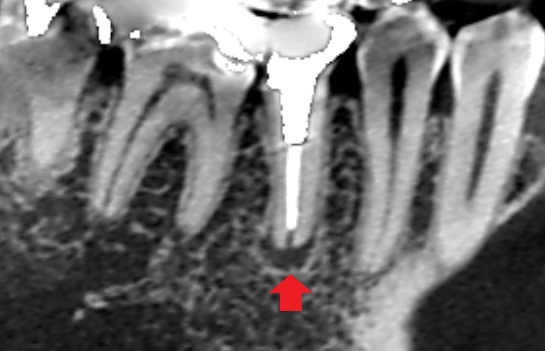

初診時のCT画像です。

赤い矢印の先に膿の影がみられます。